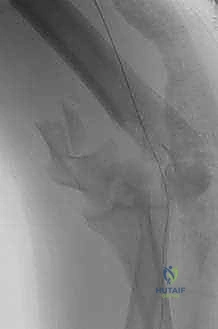

التصوير الإشعاعي المتقدم:

- الأشعة السينية (X-rays): صور أمامية خلفية (AP) وجانبية (Lateral) لتقييم مبدئي لنمط الكسر.

- الأشعة المقطعية ثلاثية الأبعاد (3D CT Scan): يعتبر الدكتور هطيف هذا الفحص إلزامياً في جميع كسور عظم العضد البعيد المفصلية. تتيح الأشعة المقطعية رؤية حجم وشكل وموقع كل شظية عظمية مهما كانت صغيرة، مما يسمح بوضع خطة هندسية دقيقة للجراحة قبل فتح المريض.

5. التثبيت الداخلي (Internal Fixation) بالصفائح والمسامير

بعد استعادة شكل المفصل، يجب تثبيته بقوة بعمودي عظم العضد (الإنسي والجانبي). يستخدم الأستاذ الدكتور محمد هطيف الصفائح التشريحية ذاتية القفل (Anatomical Locking Plates) المتطورة. هذه الصفائح مصممة خصيصاً لتناسب شكل عظم العضد الأيمن أو الأيسر.

يتم وضع صفيحتين عادة:

* التثبيت المتوازي (Parallel Plating): وضع صفيحة على الجانب الإنسي وأخرى على الجانب الجانبي، وهي الطريقة الأقوى ميكانيكياً.

* التثبيت المتعامد (Orthogonal Plating): وضع صفيحة على الجانب الإنسي وأخرى على السطح الخلفي للجانب الجانبي.

يتم تثبيت الصفائح بمسامير قفل تتشابك مع الصفيحة نفسها، مما يوفر ثباتاً استثنائياً حتى في العظام الضعيفة أو المصابة بالهشاشة.